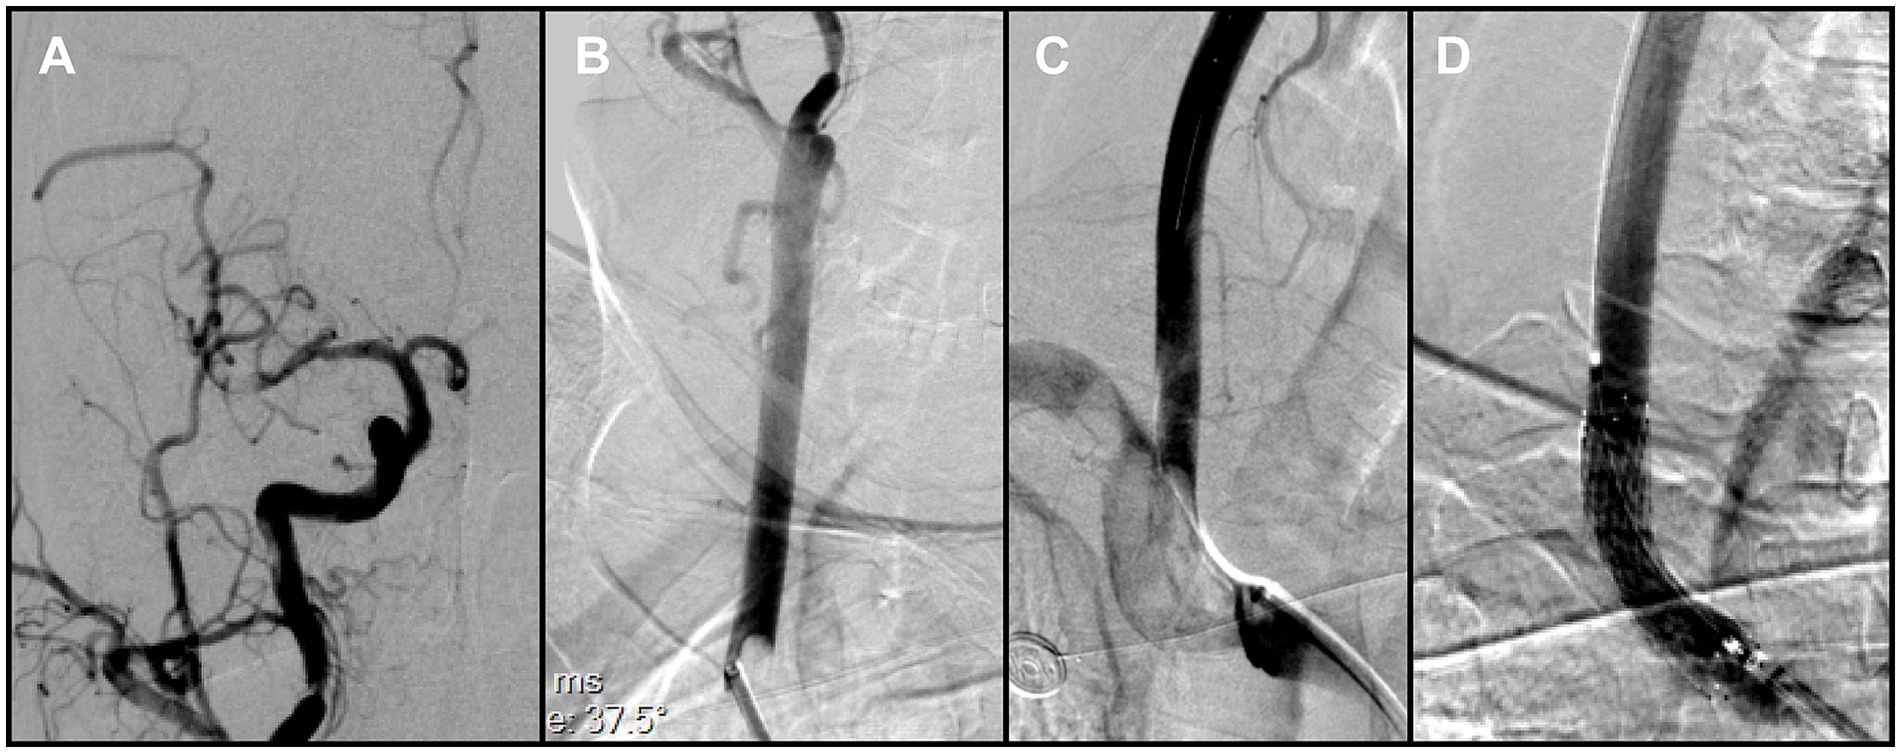

Because en bloc retrieval across the bifurcation carried high risk of embolic escape and recurrent cerebral embolism, an in situ stabilization strategy was selected. Under distal protection with a SpiderFX device, a self-expanding PROTÉGÉ 9 × 40 mm stent (Medtronic, USA) was deployed in the CCA to pin and compress the thrombus against the vessel wall without predilation. Post-deployment angiography confirmed the ICA remained widely patent, with no residual stenosis (Figure 3D). The previously noted intracranial emboli had resolved spontaneously, and the final reperfusion grade improved to mTICI 2C (Figures 4A,B). Before completion of the procedure, angiography of the left vertebral artery demonstrated patent posterior circulation vessels with retrograde opacification of the right vertebral artery, indicating preserved collateral flow and minimal risk of thrombus migration from the right subclavian artery into the intracranial circulation (Figure 4C).

Figure 4. (A,B) Final angiography prior to procedural completion demonstrated reperfusion of the right carotid system (mTICI grade 2C). (C) Left vertebral angiography showed retrograde flow in the right vertebral artery. (D) Follow-up CTA at 1 month demonstrated persistent occlusion of the right subclavian artery.

Following stent deployment, tirofiban was given as a loading infusion (0.4 μg/kg/min for 30 min) followed by continuous infusion (0.1 μg/kg/min). To reduce the risk of further cardioembolic events, therapeutic low-molecular-weight heparin (100 IU/kg once daily) was added postoperatively. During the first 24 h, platelet function and coagulation parameters were monitored every 12 h. At 24 h, follow-up non-contrast CT revealed a localized PH1-type hemorrhage as defined by ECASS. In accordance with our institutional protocol, tirofiban was discontinued and replaced with oral clopidogrel 75 mg once daily, while low-molecular-weight heparin was continued. On postoperative day 3, repeat CT showed partial resolution of the hemorrhage, indicating reduced periprocedural bleeding risk. The regimen was therefore adjusted to clopidogrel 75 mg once daily in combination with dabigatran 110 mg twice daily. According to institutional practice, this dual therapy was planned for 3–6 months, with follow-up CTA at 1 month and 6 months, and DSA at 12 months to confirm stent apposition and thrombus resolution.

Follow-up CTA at 1 month confirmed persistent occlusion of the right subclavian artery (Figure 4D). Clinically, the patient remained asymptomatic, with no upper-limb ischemic symptoms and no significant inter-arm blood pressure difference. Conservative management was therefore adopted, with surveillance imaging as planned. Referral for vascular surgical or endovascular revascularization was reserved for the development of arm ischemia, disabling symptoms, or a hemodynamically significant inter-arm pressure discrepancy. The patient showed marked neurological improvement and was discharged on the above regimen. At the 3-month clinical follow-up, the modified Rankin Scale (mRS) score was 0, indicating complete functional recovery.